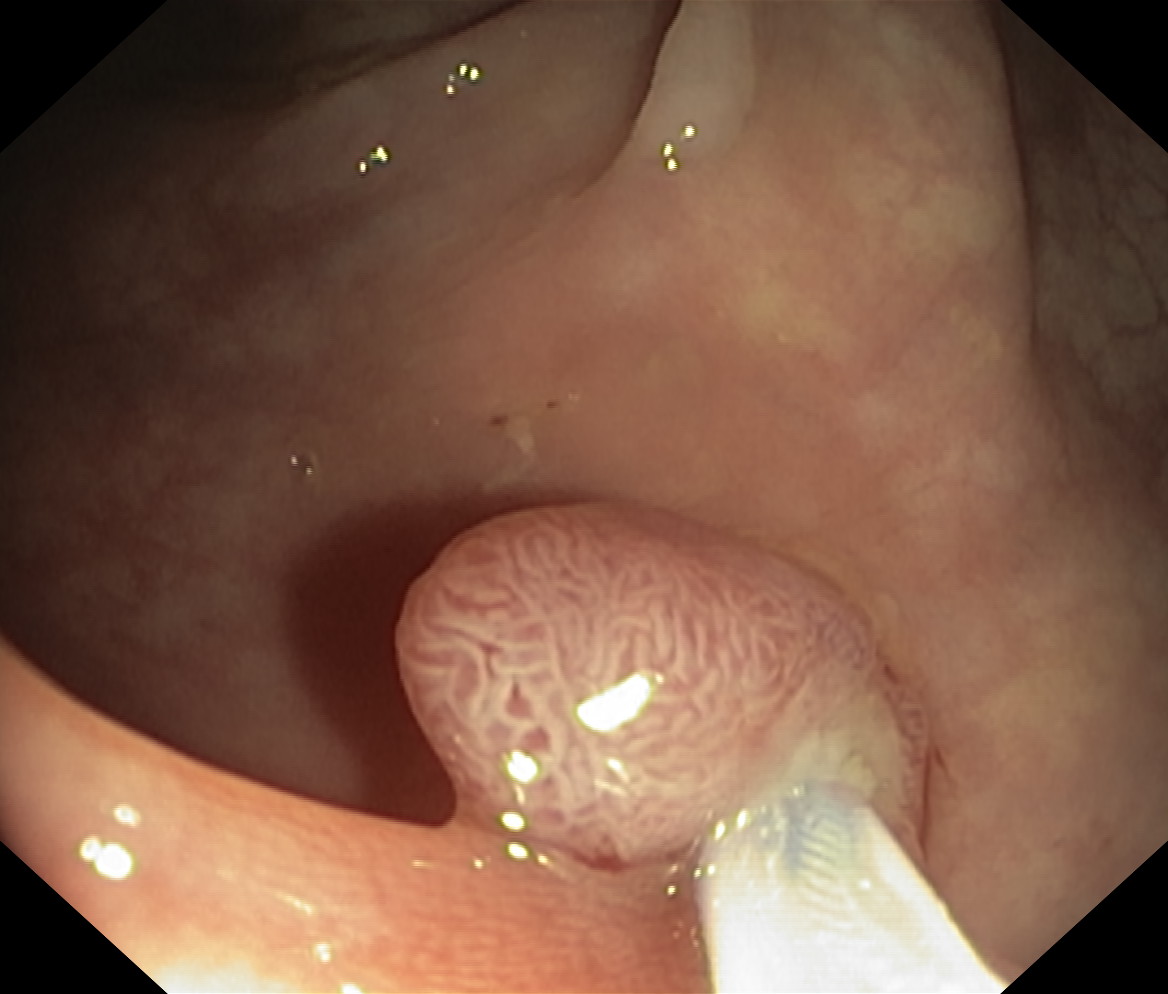

Polipy